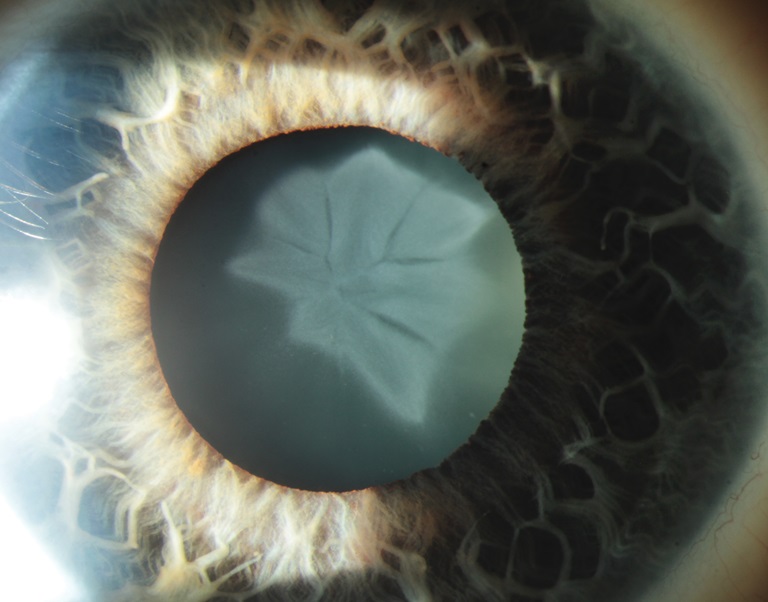

Cataracta Traumatica

Presented by Nicole MantelThis photograph received Honorable Mention in the category "Slit Lamp Photography" and was displayed at the 2024 ASCRS/OPS Society Exhibit.